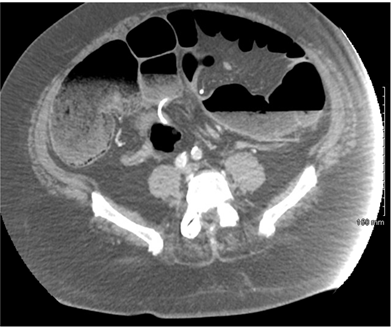

A 64-year-old male with a past medical history of diabetes, morbid obesity (BMI 44), prior surgical history of LAGB placement unknown years before, resulting in a reported 100 pound weight loss, presented to the emergency department with three days of abdominal pain. He reported his pain worsened over that timeframe with associated nausea. He denied any bowel function in the form of flatus or bowel movement. He was not in acute distress. Abdominal exam was pertinent for diffuse tenderness with rebound and guarding. Lab values were pertinent for a leukocytosis of 19, neutrophils of 92.7, hemoglobin of 16.8, platelets 499. Basic metabolic panel included glucose 315, BUN 22, Creatinine 1.2, Sodium 136, Potassium 3.7, Chloride 102, CO2 15, Anion gap 19, Lactate 4.1. His venous blood gas revealed a pH 7.182, pCO2 61.8, pO2 25, bicarbonate 23.7, and base excess -5.6. A CT scan of the abdomen and pelvis identified a large bowel obstruction at the level of the mid sigmoid colon with the LAGB catheter looped along the sigmoid mesentery in the pelvic inlet, as depicted in Figures 1 and 2. After resuscitation with 2 liters of crystalloid the patient was transferred urgently to the operating room for exploratory laparotomy. Intra-operatively marked dilation of the entire intestinal tract and a large loop of sigmoid colon was found to be strangulated by several loops of the LAGB catheter that wrapped along the rectosigmoid mesentery. The large bowel was decompressed proximally and distally with needle catheter suction. The enterotomies were closed with a figure of eight 3-0 polysorb suture. The sigmoid colon appeared dark and hemorrhagic as well. After extensive lysis of adhesions the catheter was excised and trimmed flush with the LAGB reservoir at the upper abdomen. The sigmoid colon was observed as it regained a viable color after a few minutes. In addition the mesenteric pulse was palpable. The abdomen was closed with a running 0 Maxon suture and the patient tolerated the procedure well. Post-operatively the patient progressed uneventfully. His discharge was delayed due to newly diagnosed hypertension, however once optimized he was discharged on post-operative day 7 (Figures 1) (Figures 2).

Figure 2 Sagittal CT of Acute Large Bowel Obstruction.